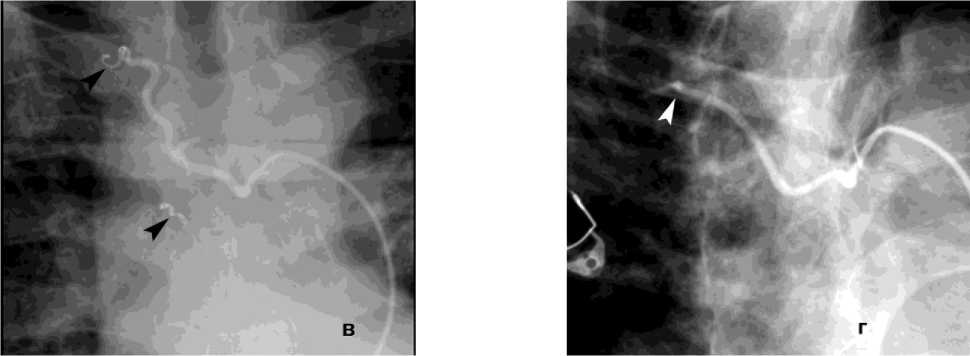

Рисунок 7. Ангиограммы правой бронхиальной артерии (ПБА) и правой межреберной артерии (ПМА) у пациента с кистозным образованием S2 правого лёгкого, ЛК1А: а, б – выраженная гиперваскуляризация дистального русла с ранним венозным сбросом в лёгочные вены; в – состояние после эмболизации ПБА микроспиралями; г – состояние после эмболизации ПМА циллиндрическими микроэмбо- лами (800 мкм)

Figure 7. Angiograms of the right bronchial artery (RBA) and right intercostal artery (RIA) in a patient with a cystic lesion in S2 of the right lung, PH grade 1A: a, б – marked hypervascularization of the distal vascular bed with early venous shunting into the pulmonary veins; в – status post embolization of the RBA with microcoils; г – status post embolization of the RIA with cylindrical microembolic particles (800 μm)

Рецидив ЛК после эмболизации наблюдался у 15 (10%) пациентов, в 3 случаях из них эмболизация БА была выполнена более года назад. В результате ангиографического поиска выявлены дополнительные источники ЛК: межреберные артерии – 4, внутренняя грудная артерия – 8 (рис. 8), АV – 3 (рис. 7).